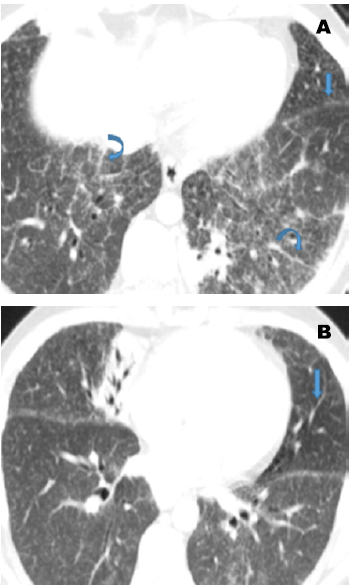

Hace más de 40 años Siltzbach desarrolló un sistema de clasificación para la sarcoidosis basado en un patrón de hallazgos radiológicos que aún es ampliamente usado y tiene valor pronóstico. Esta clasificación define 5 estadios de sarcoidosis resumidos en la (Tabla 3). Cada estadio se relaciona con una probabilidad de remisión espontánea, siendo de un 60-90 % en los pacientes con enfermedad estadio 1, 40-70 % con enfermedad estadio 2 (Figura 2), 10-20 % de pacientes con enfermedad estadio 3 y 0 % de pacientes con estadio 4 (23,24).

Este sistema de clasificación fue desarrollado antes de la introducción de la tomografía computarizada (TC) y la información recolectada hasta el día de hoy con respecto al pronóstico está basada en los hallazgos en radiografía, no en TC. La TC de alta resolución es más sensible que la radiografía en la representación de anormalidades sutiles del parénquima pulmonar en un estadio temprano de la enfermedad, aún en el estadio 1 (21,25); sin embargo, el valor del pronóstico para los hallazgos tomográficos aún no se ha estudiado ampliamente (26).

HALLAZGOS EN LA TOMOGRAFÍA COMPUTARIZADA DE ALTA RESOLUCIÓN

La TC de alta resolución es superior a la convencional en la evaluación y diferenciación entre inflamación y fibrosis en pacientes con sarcoidosis pulmonar (27,28). Su mejor resolución espacial permite mejorar la detección de opacidades reticulares, nodulares, engrosamiento de septos interlobulares y opacidades en vidrio deslustrado. La TC de alta resolución también tiene mayor utilidad en la diferenciación entre inflamación activa y fibrosis irreversible en pacientes que presentan la enfermedad en el estadio 2 o 3. Los nódulos, las opacidades en vidrio deslustrado y las opacidades alveolares sugieren una inflamación granulomatosa que puede ser reversible con terapia (29). Por el contrario, los quistes en panal de abejas, las bandas septales gruesas, distorsión de la arquitectura, pérdida de volumen y bronquiectasias de tracción indican una fibrosis irreversible. La tomografía de alta resolución también puede ser útil para comprobar el diagnóstico en pacientes con manifestaciones clínicas atípicas o que presenten hallazgos radiológicos inusuales (30).

Las opacidades en vidrio deslustrado se presentan en aproximadamente el 40 % de los pacientes y se originan por la confluencia de múltiples lesiones intersticiales granulomatosas micronodulares y fibróticas, lo que genera compresión pero no el llenado del espacio aéreo visto en la alveolitis (25,27). El patrón de atenuación en mosaico en pacientes con sarcoidosis es resultado del compromiso de la pequeña vía aérea por granulomas o fibrosis, lo cual puede originar una obstrucción y asociarse al atrapamiento aéreo, este último es mejor visualizado en las fases espiratorias (32,33).

Finalmente, se pueden ver cambios fibróticos que desarrollan hasta un 20 % de los pacientes, dentro de los cuales se encuentran la presencia de bandas septales gruesas, distorsión de la arquitectura, pérdida de volumen, quistes en el panal de abejas y bronquiectasias de tracción, hallazgos indicativos de fibrosis irreversible (34). Son más frecuentes en los campos pulmonares medios y superiores, con una distribución parcheada. En casos avanzados se pueden asociar a una hipertensión pulmonar y/o insuficiencia cardiaca derecha. Otras manifestaciones radiológicas menos frecuentes no se abordarán en la presente revisión.